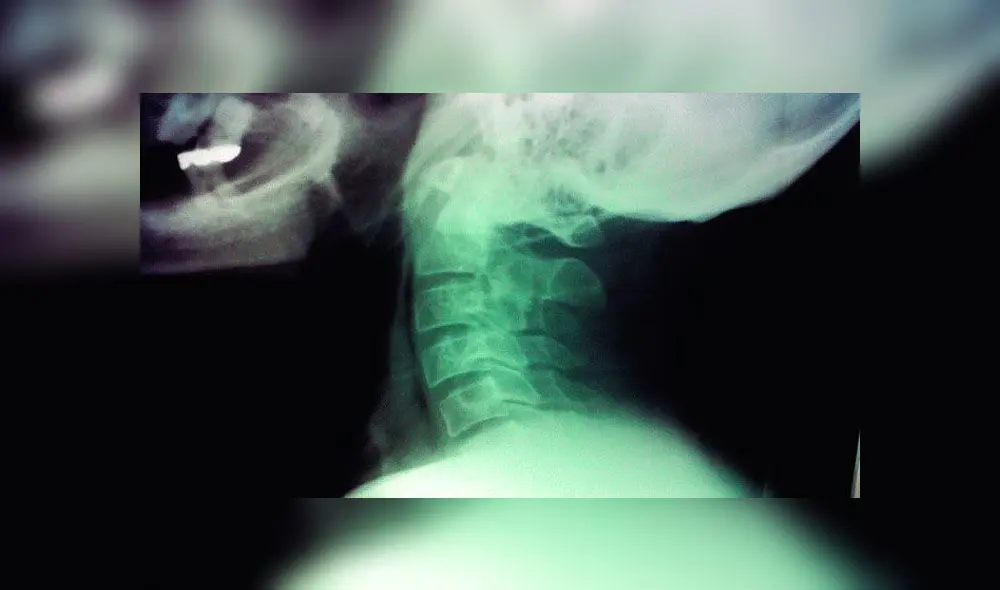

Según su investigación publicada en la revista Journal of Anatomy, el bulto aparece en la parte posterior de la cabeza, un poco encima del cuello. Este puede sentirse al tacto y hasta resulta visible en algunas personas con calvicie.

El trabajo científico del doctor David Shahar en Australia analizó en 2016 a 218 personas de entre 18 y 30 años de edad. De estos se demostró que el 41 % de los participantes tenía en la cabeza ‘picos’ de más de 10 milimetros, mientras que el de un 10 % superaba los 20.

En 2018, Shahar se centró en determinar las edades de las personas que contaban con esta deformación en el cráneo. De los 1 200 participantes de entre 18 y 86 años, el estudio científico concluyó que era “significativamente más probable” encontrar abultamientos entre los participantes de 18 y 30 años.

Shahar sostiene que cuando nos inclinamos para ver las pantallas, los músculos del cuello se tensan para sostener la cabeza, que pesa aproximadamente 5 kilos.

Debido a la gran presión que ejerce el cráneo sobre el cuello es el lugar apropiado para que aparezca este ‘pico’, debido a que el cuerpo trata de adaptarse para aliviar la presión creando nuevos huesos.